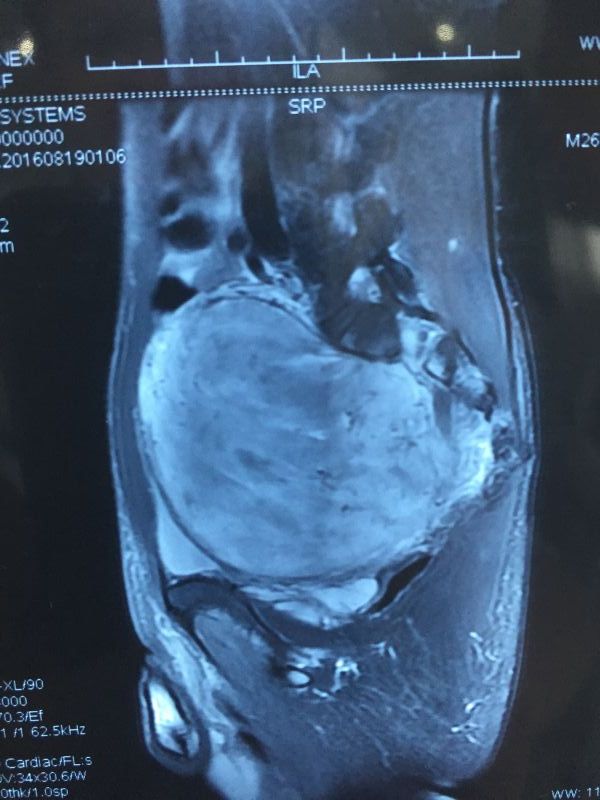

27岁的安庆小伙小陈在武汉工作,一个多月以来老是感觉腹痛腹胀,有时会呕吐,新婚的妻子赶紧陪他去医院检查。没想到,一纸B超单打破了他幸福平静的生活。小陈的盆腔内“藏”了一个大肿瘤,有一个小皮球那么大,占据了整个盆腔。

经过进一步检查,小陈的肿瘤达到了154mm*117mm*111mm,肿瘤的压迫已经导致小陈双肾积水,肾功能不全。为了避免病情进一步恶化,我院胃肠外科二病区主任医师曹先东紧急联系神经外科副主任医师王卫红进行会诊,决定实施肿瘤摘除手术。在麻醉科、手术室等科室的密切协作下,8月25日,手术顺利进行。

巨大的肿瘤“挤满”整个盆腔,导致髂血管受压移位,双侧输尿管、直肠都受到严重挤压,手术前膀胱镜置双“J”管未能成功。曹先东介绍,考虑肿瘤来自于骶管,肿瘤表面布满血管,周围有很多神经和正常器官,稍有不慎会造成大出血或者伤及神经。男性骨盆较窄,盆腔空间本就狭小,又被肿瘤占据,几乎完全“无下手之地”,手术难度非常大。术中只能采取逐步切除的方式,渗血量达到了2000ml,经过2个半小时的紧张手术,肿瘤被完全摘除。目前,小陈恢复良好,再过一周就可以出院了。